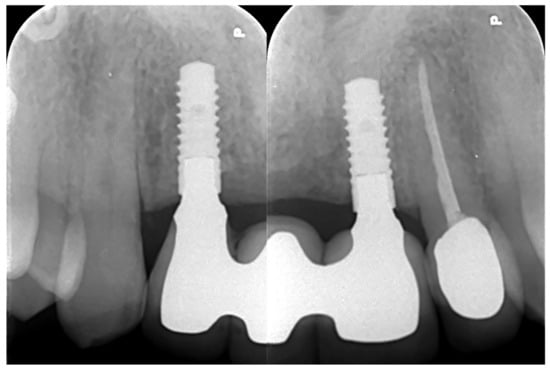

Retroalveolar radiographs showing the dental implants in place.

In November 2017, two guided dental implants were placed at sites # 12 and # 21 (Figure 7, Figure 8, Figure 9, Figure 10 and Figure 11).

6.1.5. Postoperative (5-Years Follow-Up) Documentation:

A screw-retained provisional fixed prosthesis was used for 4 months to condition peri-implant mucosa, and in January 2019, the final prosthesis was installed. The occlusion was adjusted, and the patient received instruction for oral hygiene. A follow-up assessment at 5 years showed a stable cosmetic, biological and functional reconstruction (Figure 12, Figure 13 and Figure 14).